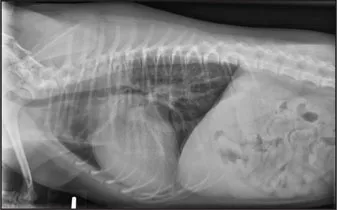

CASE 1.1 A 7-year-old neutered male Labrador Retriever who was hit by a car. You obtain these thoracic radiographs: Figs. 1.1a, b, left and right lateral projections, respectively; Figs. 1.1c, d, ventrodorsal and dorsoventral projections, respectively.

1.1b